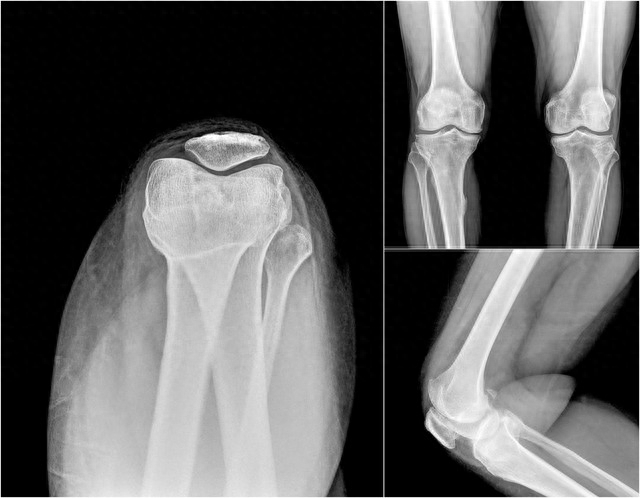

4. 影響骨骼健康:運動可以幫助維持骨密度,防止骨質疏鬆。

而長期缺乏運動,骨骼會逐漸變脆,易於發生骨折,這也是衰老的表現之一。